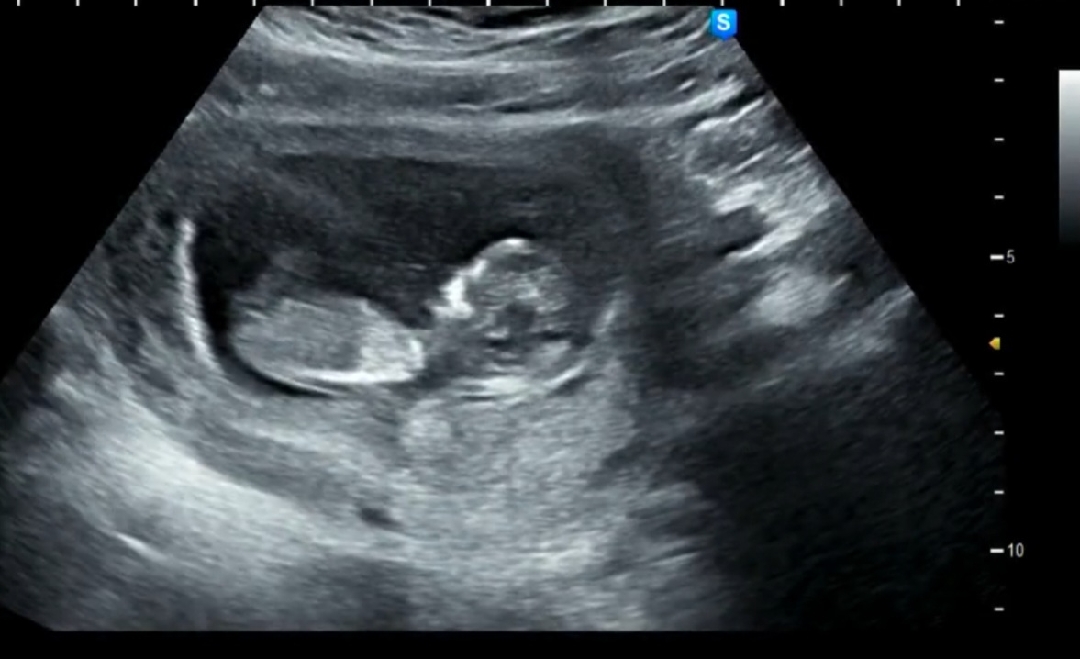

11주 4일차 각도법 부탁드려요🥰

고수님들 의견부탁드립니다~

딸에 한표요!